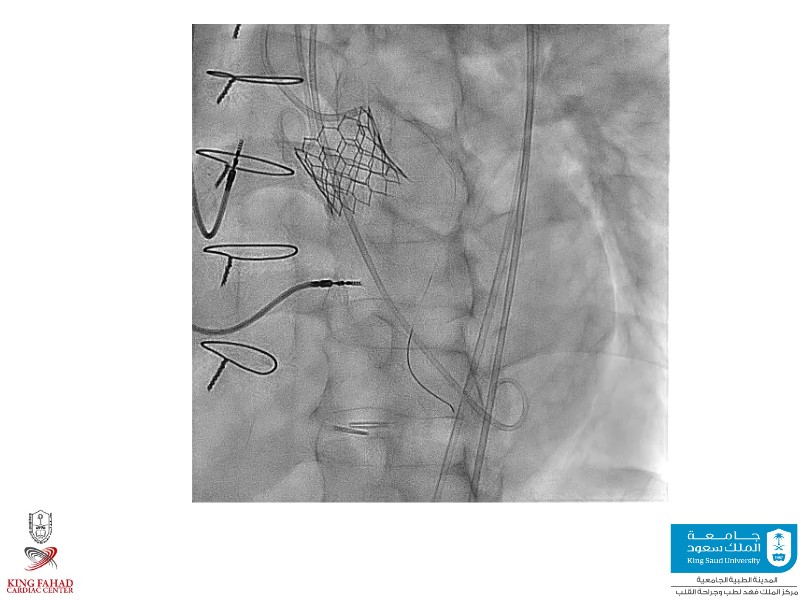

This session helps you anticipate and address complex scenarios such as mitral valve-in-valve, TAV-in-SAV, and valve-in-valve-in-valve procedures. Learn from expert case discussions that explore procedural strategies, technical challenges, and best practices to optimize outcomes in redo structural heart interventions.

- To anticipate and manage second valve scenarios with SAPIEN 3 Ultra RESILIA, including mitral valve-in-valve, TAV-in-SAV, and TAV-in-TAV

- To understand procedural strategies and challenges in complex redo scenarios using SAPIEN 3 Ultra RESILIA